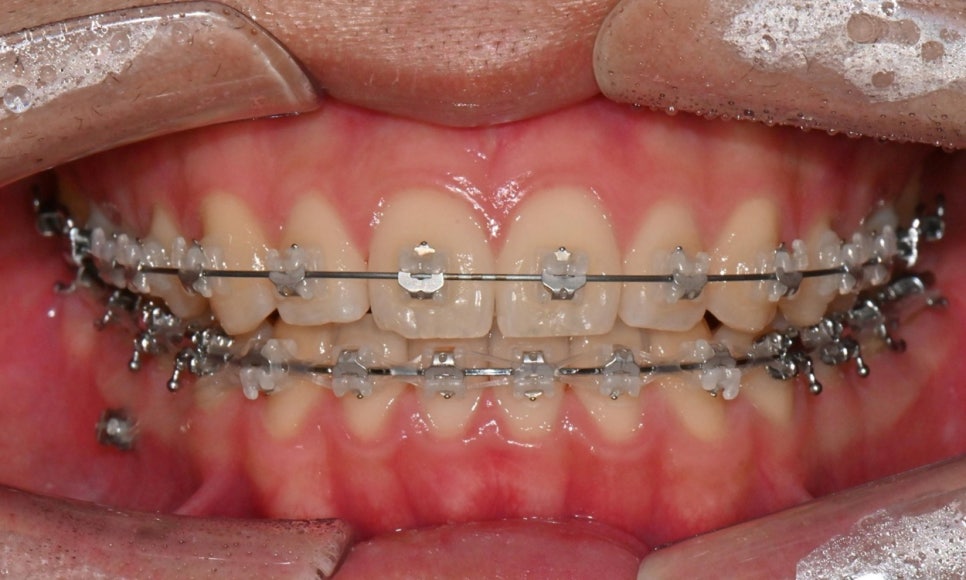

약 1년 간의 교정 치료를 통해 어긋나 있던 치아 중심선이 자연스럽게 맞춰졌고, 중심선 비대칭이 개선 및 하악 아랫입술 돌출도 눈에 띄게 호전되었습니다. 무엇보다 치료 기간 동안 앞니의 치근 흡수는 추가적인 진행 없이 안정적으로 유지되었습니다.

돌출을 조금 더 개선하는 것을 추천했으나, 환자가 갑자기 군 입대를 하게 되어 현 상태로 치료를 마무리하기로 하였습니다. 치료 전후 치아 위아래 중심선이 일치하며 좌우 어금니 교합도 향상되었습니다. 하악 치열의 후방 이동으로 아래 입술의 돌출도도 많이 개선되었습니다. 멀리서도 믿고 내원해주고, 치료 기간 동안 성실히 협조해준 환자분께 감사드리며 앞으로도 건강한 치아로 군 생활 잘 마치길 응원합니다 :)